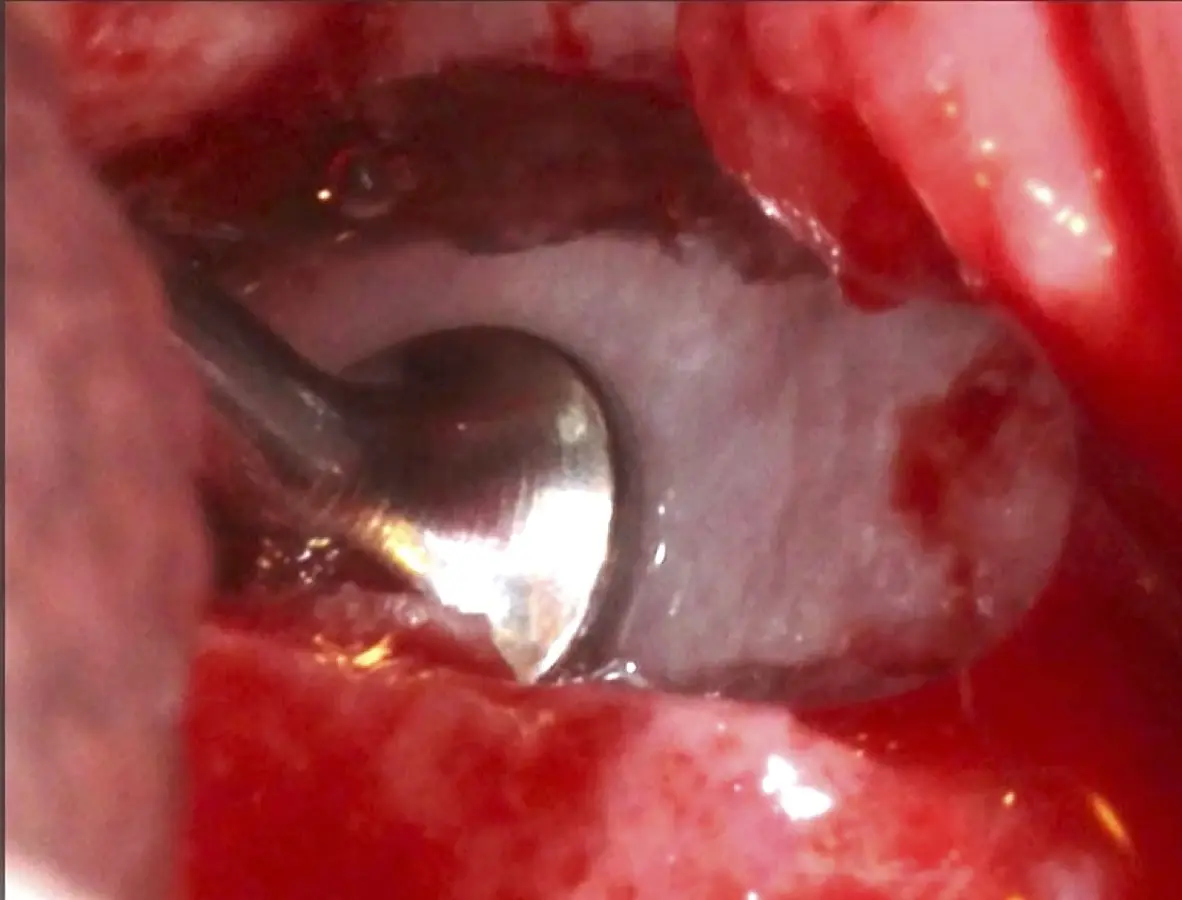

Figura 6. Técnica por retiro de la tabla ósea. Una vez retirada o fracturada la tabla ósea, se introduce el inserto de presión hidráulica entre la membrana de Schneider y los bordes de la ventana, con suaves movimientos se inicia el desprendimiento gracias al chorro de agua expulsado a través del inserto (Figura 7).

Inserto de presión hidráulica iniciando el desprendimiento de la membrana de Schneider (a, b ).

Figura 7. Inserto de presión hidráulica iniciando el desprendimiento de la membrana de Schneider (a, b ).

Figura 17. Inicio del desprendimiento de la membrana de Schneider con el inserto de presión hidráulica.

Figura 25. Introducción del bloque óseo de la pared lateral dentro del seno maxilar: inicio del desprendimiento de la membrana con el inserto de presión hidráulica.